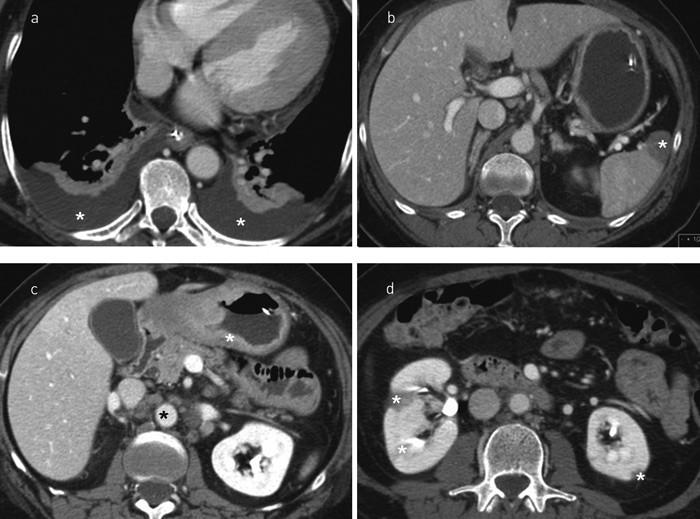

Kreftmarkøren CA 125 var 60 (0 – 35), og CT abdomen fra sentralsykehuset ble gransket på nytt. En mulig fortykket antrum ventriculi og grensestore lymfeknuter fikk ny oppmerksomhet.

CT og MR abdomen viste forverring av de nevnte funnene og infarkter i leveren og begge nyrene (fig 2). Pasienten ble gastroskopert. Biopsi fra ventrikkelen viste et lite differensiert mucinøst adenokarsinom av diffus type. Man konkluderte med at sykdomsbildet skyldtes kreftindusert hyperkoagulabilitet. Kvinnen døde dag 36.